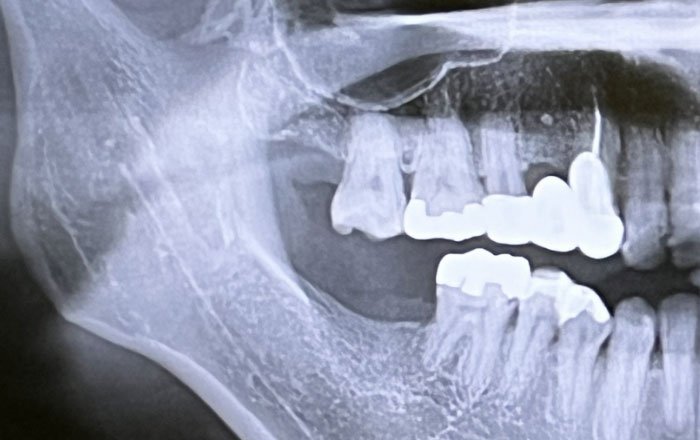

骨の変化

歯を支える土台となる歯槽骨(しそうこつ)も、年齢とともに少しずつ減少していきます。歯槽骨が減ると、歯がぐらついたり、歯並びが変わってきたりすることもあります。

歯周病の進行

8020財団のページでも掲載されているように、歯周病は歯を失う原因の第一位とされており、初期のうちは痛みや違和感が少ないため、気づかないうちに進行してしまうのが厄介です。

歯茎が腫れる・出血する・歯が揺れるなどの症状が出る頃には、すでに歯を支える骨が溶け始めていることも珍しくありません。